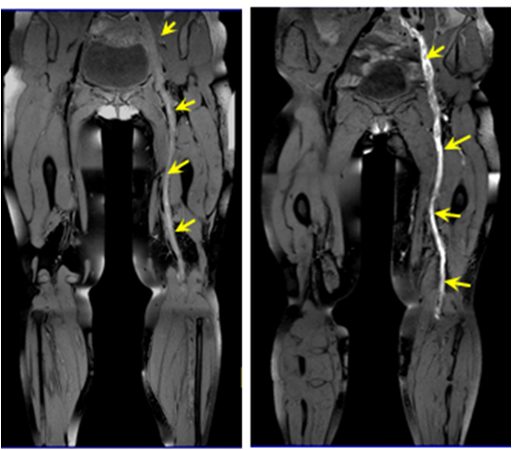

2. 不同时期血栓病人的成像结果比较,本项目提出的检查方案可以通过血栓的定量测量推出血栓的进展和分期,为临床精准化治疗提供依据